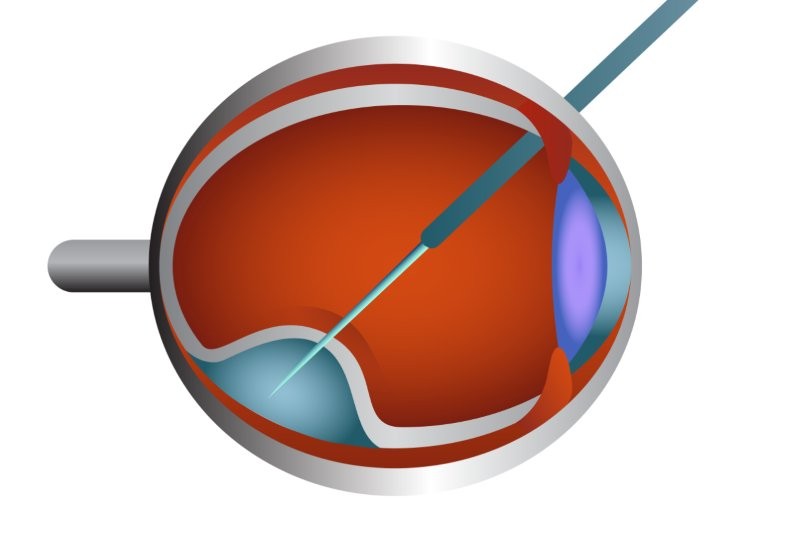

The integration of clinical and molecular data has paved the way for gene-targeted therapeutics, marking a paradigm shift in the management of IRDs. The development of such therapies depends on multiple disease- and gene-related factors. Disease-related considerations include the global burden of IRDs, degree of visual morbidity, age at presentation, disease stage and rate of progression. Gene-related factors include inheritance pattern, the functional impact of the mutation (eg. loss of function, dominant-negative effects) and practical considerations such as gene size, which influences vector-delivery strategies3 (Fig 1).

Fig 1. Routes of administration of viral and non-viral vectors in gene therapy3

A major milestone in this field was the approval of voretigene neparvovec (Luxturna), the first in vivo gene therapy approved by the US Food and Drug Administration (FDA) for retinal disease. This adeno-associated virus (AAV2)-based therapy targets biallelic mutations in the RPE65 gene and is indicated for patients with viable retinal cells. Delivered via subretinal injection, the therapy enables retinal pigment epithelial cells to produce the enzyme required for the visual cycle. Long-term studies (up to 15 years) have demonstrated sustained improvements in functional vision, including enhanced light sensitivity and navigation ability4. However, the surgical delivery carries potential risks such as endophthalmitis, retinal detachment, retinal haemorrhage, increased intraocular pressure and structural complications including foveal thinning5.